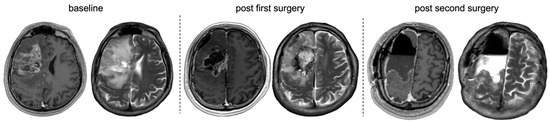

Prevalence and Clinicoradiopathological Characterization of H3 K27-Altered Diffuse Midline Gliomas in Adults—A Retrospective Observational Study

by Kristof Babarczy, Bence L. Radics, Lili Kiss, Alexandra Graczer, Bence Nagy, Sandor Dosa, Gyongyi Kelemen, Marton Balazsfi, Pal Barzo, Andras Voros, Peter Klivenyi and Levente Szalardy

Pathophysiology 2026, 33(1), 21; https://doi.org/10.3390/pathophysiology33010021 - 14 Mar 2026

Background/Objectives: Diffuse midline glioma (DMG), H3 K27M-altered, represents a rare group of gliomas arising in midline structures of the central nervous system. Historically regarded as a pediatric entity, it is now increasingly recognized in adults. Although its relative prevalence among all midline [...] Read more.

Background/Objectives: Diffuse midline glioma (DMG), H3 K27M-altered, represents a rare group of gliomas arising in midline structures of the central nervous system. Historically regarded as a pediatric entity, it is now increasingly recognized in adults. Although its relative prevalence among all midline diffuse gliomas and its clinical-radiological characteristics are well defined in children, these tumors remain less characterized in adults, and comparative evaluations with H3 K27 wildtype midline diffuse gliomas are limited. Methods: Consecutive adult patients with histopathologically confirmed diffuse glioma (WHO grade ≥ 2) diagnosed between 2016 and 2025 were retrospectively screened for midline tumor location, with systematic revision of imaging and pathology. For identified midline diffuse gliomas, comprehensive clinical, imaging, and immunohistochemical data were collected, and a detailed morphometric analysis was performed. H3 K27 alteration status was established immunohistochemically, with supplementary immunostaining when necessary. Descriptive and comparative analyses were conducted. Results: A total of 5% of the 541 adult diffuse gliomas were midline, and 23% of IDH wildtype midline gliomas were consistent with DMG, H3 K27-altered (all H3 K27M-mutant). The affected patients were significantly younger, and these tumors predominantly involved the thalamus and mesencephalon. Morphometric analyses revealed trends toward fewer high-grade features in H3 K27-altered tumors, with composite scores demonstrating significant discriminatory ability. The overall survival was not significantly different between groups but showed associations with ring-like enhancement as well as adjuvant and salvage therapies in the overall midline cohort. Conclusions: This study provides population-based prevalence estimates for DMG, H3 K27M-altered, and complements the limited literature with comparative clinical-radiological and morphometric data of potential prognostic relevance. Full article